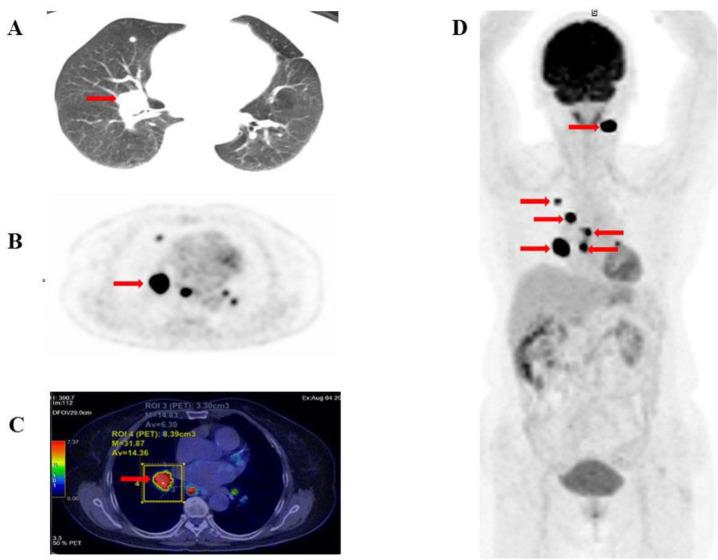

This study investigates the relationship between quantitative F-FDG PET/CT metabolic parameters and overall survival (OS) in patients with radioiodine-refractory differentiated thyroid cancer (RAI-R DTC).

We conducted a prospective analysis of 127 patients with RAI-R DTC. Quantitative metabolic parameters including SUV, SUV, SUV, total metabolic tumor volume (MTV), and total lesion glycolysis (TLG) were assessed in F-FDG -avid recurrent or metastatic lesions via F-FDG PET/CT imaging. Patients were monitored for disease progression and mortality for at least one-year post PET/CT imaging. Receiver operating characteristic (ROC) curves were used to establish cut-off values for predicting 5-year mortality, while the Kaplan-Meier method estimated the 5-year survival rate. Univariate and multivariate Cox regression analyses identified prognostic factors associated with OS.

The metabolic parameters derived from F-FDG PET/CT demonstrated high sensitivity and specificity for predicting 5-year OS. ROC curve analysis established optimal cut-off values for SUV (20.27 g/mL), SUV (7.46 g/mL), SUV (7.8 g/mL), TLG (45.74 g/mL×cm³), and MTV (5.78 cm) (AUC: 0.82, 0.78, 0.82, 0.82, and 0.86, respectively; p<0.001). Kaplan-Meier analysis revealed significantly lower OS in patients with higher values of these parameters compared to those with lower ones (survival rates: 42.1% vs. 95.6%, 65.5% vs. 96%, 52.3% vs. 96.3%, 46.5% vs. 97.3%, and 57.3 % vs. 98.3%, respectively; p<0.001). Univariate Cox regression identified SUV, SUV, SUV, TLG, and MTV as significant predictors of 5-year OS (p<0.05). In multivariate analysis, SUV and MTV emerged as independent predictors of OS.

Quantitative F-FDG PET/CT-derived parameters are significant predictors of 5-year OS, exhibiting high sensitivity and specificity. Elevated values of these parameters correlate with increased mortality rates. Our findings suggest that SUV and MTV are independent prognostic factors for 5-year OS in patients with radioiodine-refractory DTC.